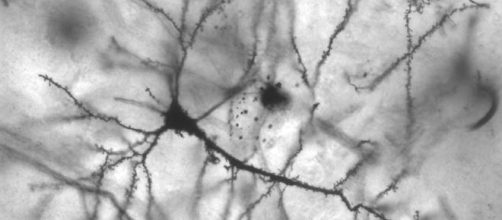

Cuando el cerebro recibe información sensorial, la actividad neuronal genera unos patrones determinados. Según ciertas investigaciones, para que exista la consciencia, es necesario que los patrones neuronales que se forman ante cada percepción se mantengan estables durante algunos cientos de milisegundos.

En el nuevo experimento, se ha observado la actividad cerebral de 116 personas con trastornos de la consciencia, desde estados vegetativos a pacientes recién salidos de un coma o mínimamente conscientes. Los resultados muestran que la estabilidad de los patrones cerebrales tras una percepción dura más cuanto más consciente es la persona. Esto aporta nuevos argumentos a los defensores de la teoría del espacio de trabajo global, propuesta por Bernard Baard en la década de 1990.

La investigación de Schurger proporciona nuevos datos empíricos que muestra que, para que la consciencia sea posible, es necesario que las diferentes áreas del cerebro permanezcan sincronizadas durante algunas centésimas de milisegundo antes de romperse el patrón.